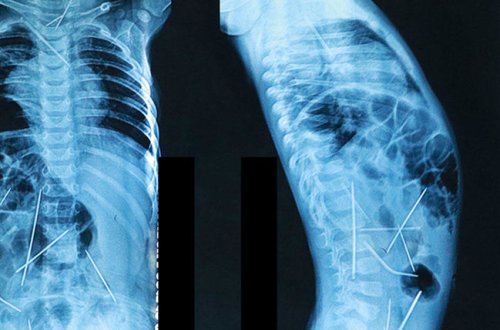

11 aylıq uşağın bədənində 16 iynə tapıldı -

uşağın

görə

iynələri

bədənində

dediyinə

deyib

iynə

cərrahiyyə

əməliyyatı

bədəninə

yanvarın

səbəbini

düşdüyünün

qadın

sakini

hələlik

akilov

xəstəxanaya

sözlərinə

vilayətinin